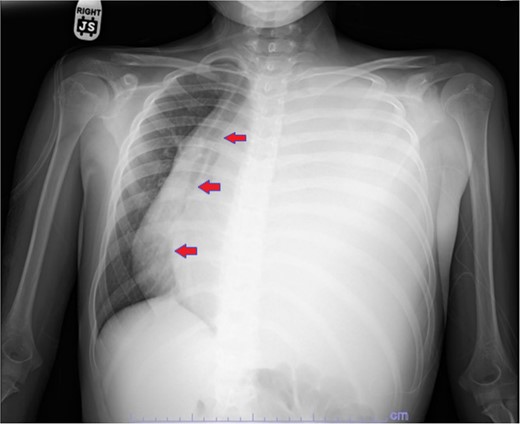

Our patient is a 10-year-old Caucasian female with a history of early adrenarche, ADHD, and COVID-19 and no past surgical history. She presented to the ED with a month-long history of persistent coughing, shortness of breath on exertion and speaking, and left-sided chest pain that began after a diagnosis of mildly symptomatic COVID-19. A physical exam revealed decreased breath sounds on the left, with a left-sided chest protrusion. A plain film and CT demonstrated a normal right lung, with a significant mediastinal shift toward the right, displacement of the heart into the right hemithorax, with complete whiteout of the left hemithorax, and demonstrating a mix of solid and cystic foci, with a round opacification at the left lung base (Figs 1 and 2). The patient underwent an uncomplicated left thoracotomy with excision of two masses, one being 22.5 × 21.0 × 10.5 cm and the other being 13.5 × 11.5 × 6.2 cm. These masses weighed 2394 g in aggregate. The specimens consisted of well-encapsulated tumors attached to the posterior aspect of the chest wall. A regional, positive lymph node measuring 3.0 × 2.2 × 1.0 cm was also resected. Due to the large size of the tumor and the requirement for clean margins, parts of the latissimus dorsi and serratus anterior muscles were also resected. By postoperative day (POD) 0, the left lung had already filled the left hemithorax, and the mediastinal shift had corrected (Fig. 3). The chest tube was removed on POD 5, and a plain film showed continued expansion of the lung to full size and resolving pulmonary edema and atelectasis (Fig. 4). The patient was discharged home on POD 5. The tumor staging was T4N1M0. The tumor was positive for vimentin, CD56, synaptophysin, chromogranin, and NSE. The tumor was negative for pancytokeratin, Cam5.2, EMA, S100, desmin, SMA, SOX10, HMB45, CD117, DOG1, CD99, PR, CD68, WT1, CD30, p53, Alk1, GFAP, and nuclear β-catenin. Next-generation sequencing showed an MGA:NUTM1 fusion, supporting a final diagnosis of high-grade MGA:NUTM1 fusion SCS. Given the size and grading of the tumor, the patient underwent adjuvant CT-RT with ifosfamide, doxorubicin, and proton beam radiotherapy, with supportive doses of MESNA and dexrazoxane for 4.5 months post-operatively. The basis of this treatment is ARST0332 Arm C [6]. Before treatment initiation, the patient underwent an uncomplicated left oophorectomy for reproductive cryopreservation. A PET/CT prior to CT-RT showed hypermetabolic activity in several areas. These included the pleural resection margin, a mediastinal lymph node concerning for metastasis versus postsurgical change, and a left axillary lymph node concerning for metastatic disease. During treatment, the patient contracted human metapneumovirus and rhino/enterovirus, resulting in febrile neutropenia. The patient was successfully treated with blood and platelet transfusions and pegfilgrastim. Upon completion of CT-RT, PET/CT imaging showed no evidence of residual disease, with minimal focal hypermetabolic activity as compared to the previous imaging (Fig. 5).

Plain film postoperative day 5, after removal of chest tube, showing improving pulmonary status in the left hemithorax.